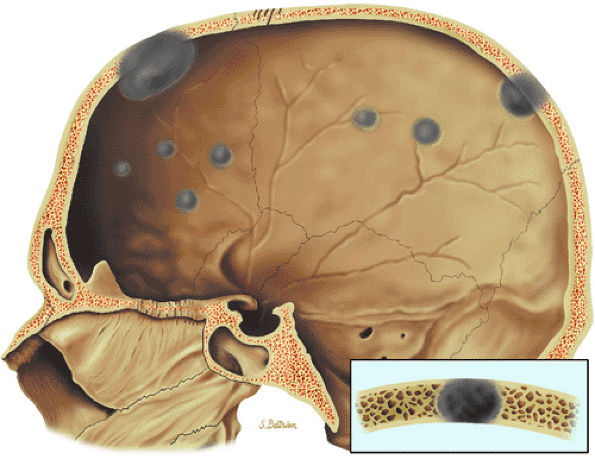

|

FIGURE 13.43 ● Multiple punched-out lesions are seen as gray areas of the skull on this sagittal graphic illustration.